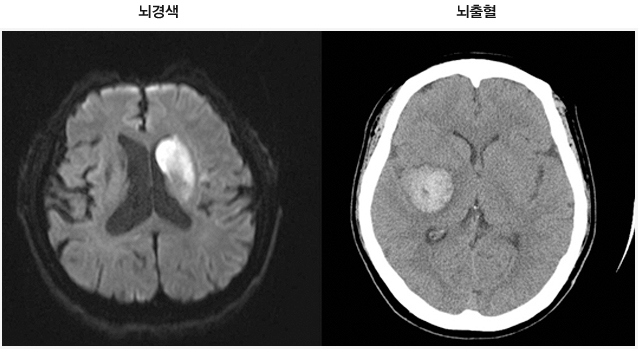

뇌경색은 혈관이 좁아지거나 막히면서 발생하는 뇌의 손상입니다. 이는 주로 혈전이나 색전으로 인해 발생하며, 그로 인해 뇌의 특정 부분에 oxygen과 영양소가 공급되지 않게 됩니다. 이 상태가 지속되면 뇌세포는 영구적으로 손상을 입거나 죽게 됩니다.

뇌경색에는 두 가지 주요 유형이 있습니다. 첫 번째는 허혈성 뇌경색으로, 대개 혈전이 혈관을 막아 발생합니다. 두 번째는 출혈성 뇌경색으로, 뇌혈관이 파열되거나 약해져 출혈이 발생하는 것입니다. 본 포스팅에서는 주로 허혈성 뇌경색의 초기 증상에 대해 설명드리겠습니다.